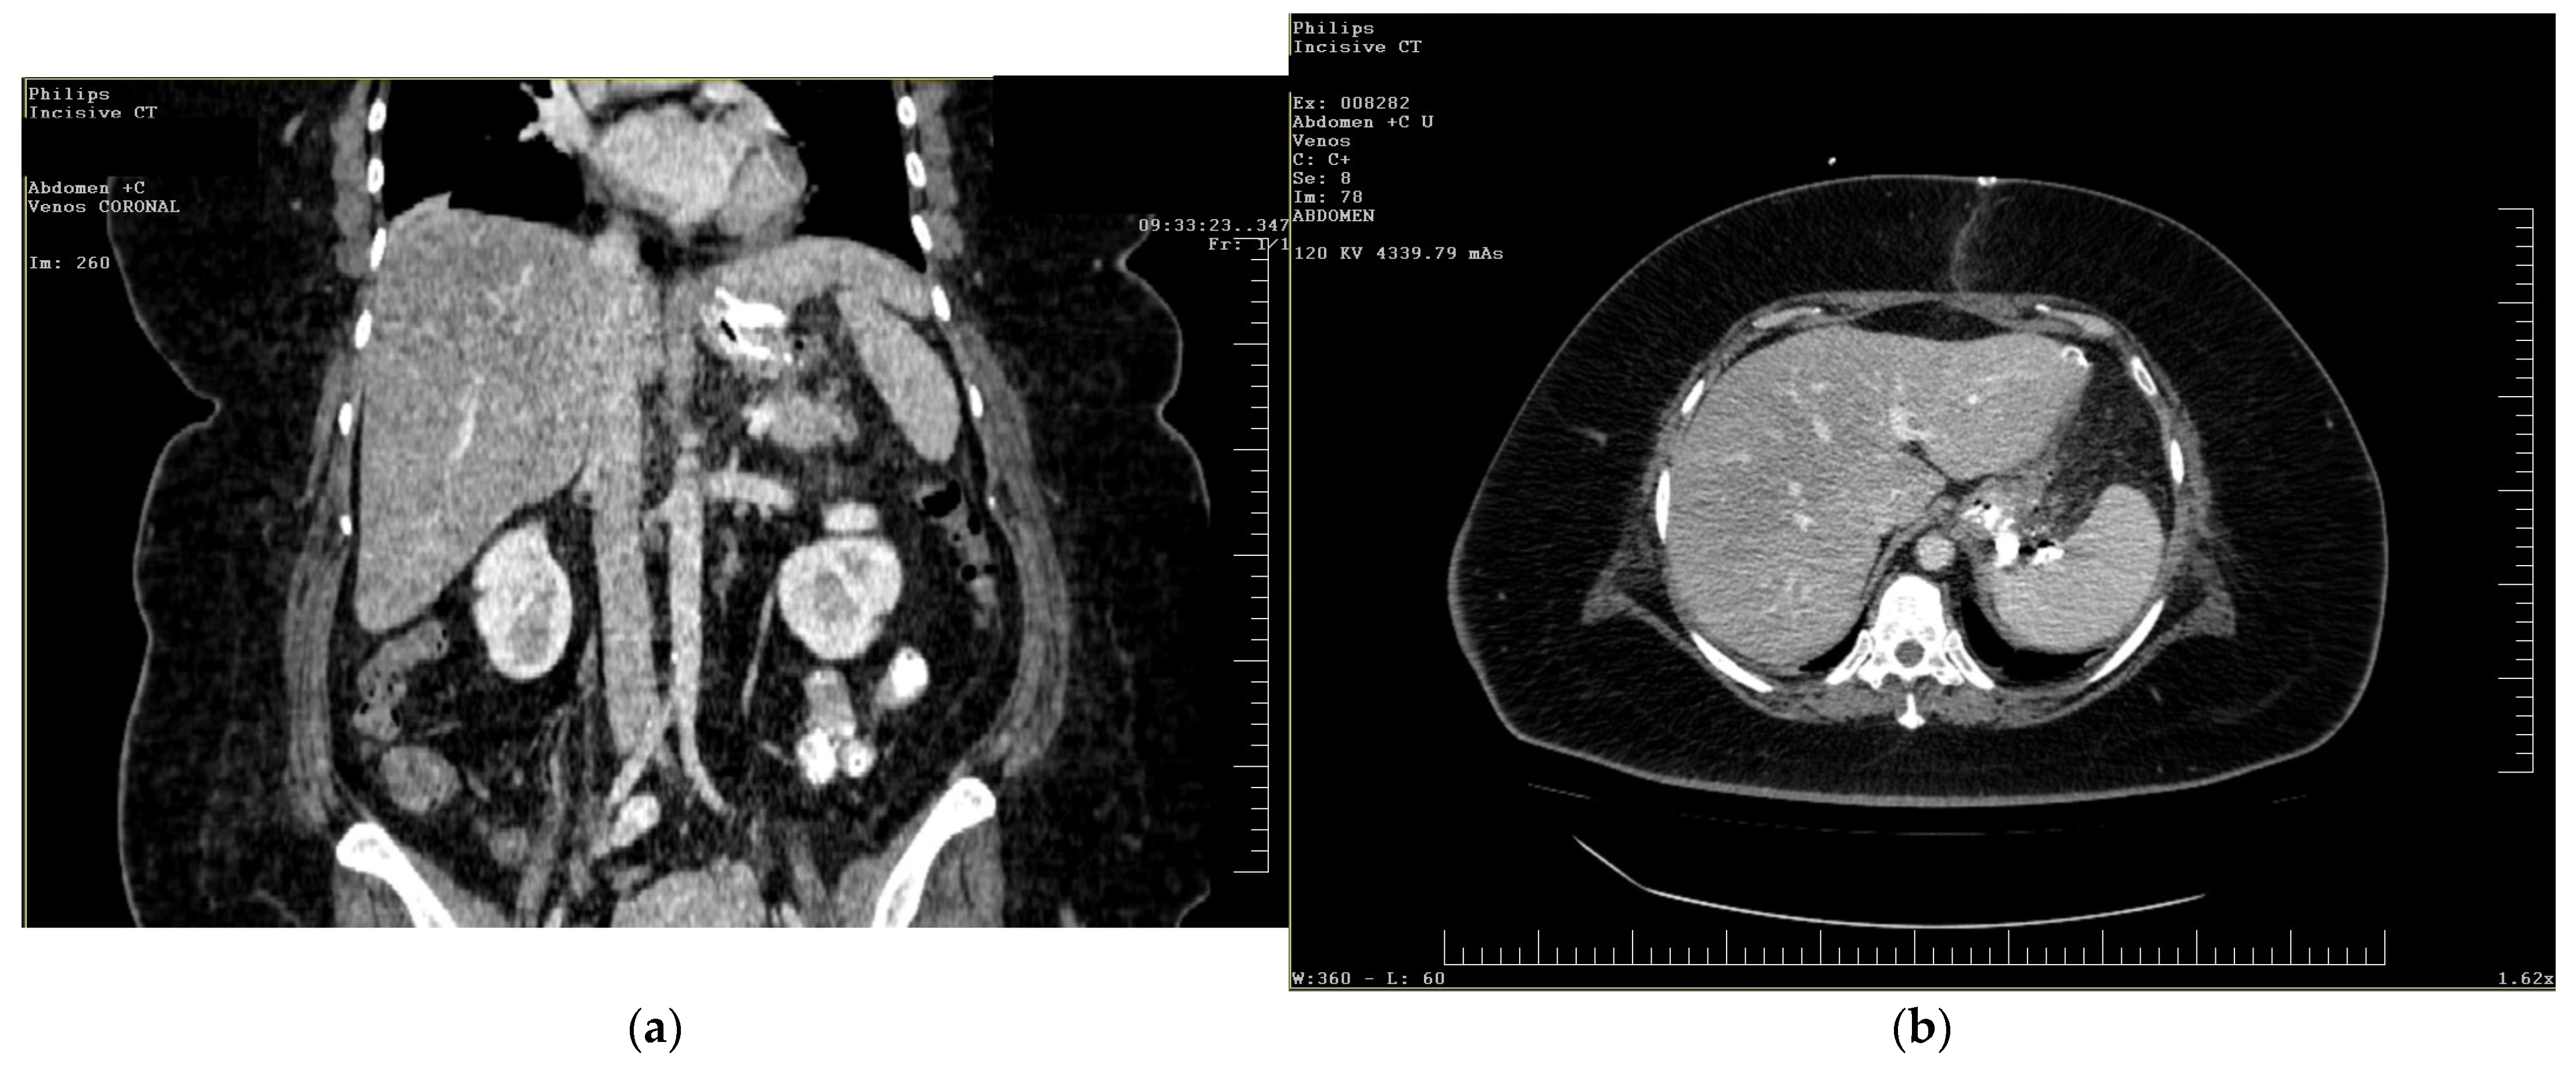

To gain a more comprehensive understanding of the patient’s condition, a contrast-enhanced abdominopelvic computer tomography (CT) scan was performed. Imaging revealed a reduced gastric volume with the nasogastric tube in place, previously positioned with its distal tip at the subcardial region (Figure 1a,b). In the gastric fornix, two parietal defects were observed, measuring 13 mm (on the posterior wall) and 3 mm (on the anterior wall), with the passage of orally administered contrast substance into the fat of the gastro-splenic ligament. Near the greater curvature of the stomach, a few gas bubbles were present in the omental fat. Further investigations were carried out, including an endoscopic examination, which revealed the esophagus with a 20 mm lumen and tertiary contractions. Additionally, a highly intense pneumatosis was observed throughout the entire colonic frame. The contrast agent administered during the procedure was later detected at the level of the left colon, further guiding the diagnostic process. Following this thorough clinical and paraclinical evaluation, the diagnosis of a high gastric fistula secondary to a gastric sleeve procedure was confirmed.

Figure 1.

(a,b) Abdominal computer tomography (coronal and axial view)—parietal defects are observed with the presence of the contrast substance in abdominal cavity.